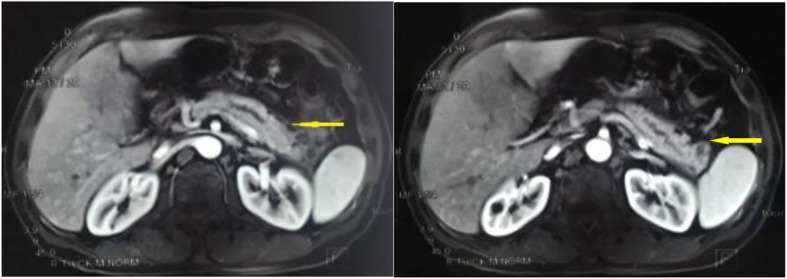

A 47-year-old male patient suffering from mild abdominal pain for 2 months was admitted to our hospital in February 2018. He was diagnosed with “acute pancreatitis” first before transferring to our department. The ultrasound (US) and computed tomography (CT) scan of the abdomen revealed a pancreatic space-occupying lesion and pancreatic duct dilatation (Fig. 1). The serum amylase and lipase levels were slightly elevated (231 and 546 U/L, respectively; normal range: 25–125 and 13–60 IU/L, respectively). the preoperative serum CA 19–9 level was 34.82 U/ml. Then, the patient underwent exploratory laparotomy. Intraoperative examination identified a hard mass in the body (approximately 4.0 cm × 3.0 cm) and tail of the pancreas, varicose veins around the spleen, a mass in the diaphragm (1.5 cm diameter), and three light masses on the surface of the liver. One mass was taken for pathological examination of the intraoperative rapid frozen section, and the result showed adenocarcinoma in the mass. The patient underwent radical distal pancreatectomy, splenectomy, diaphragm, and liver mass resection. The patient manifested with obstructive jaundice after surgery and gradually increased level of bilirubin. The total bilirubin increased from 65.4 μmol/L to 105.6 μmol/L and then to 140.1 μmol/L, and the direct bilirubin increased from 53.8 μmol/L to 81.0 μmol/L and then to 118.1 μmol/L. Subsequently, the patient underwent cholangiojejunostomy, and the pathological report revealed resected masses from the pancreas, liver, and diaphragm, indicating PTC metastases (Fig. 2). Immunohistochemical studies showed positive stanning of TG(+), PAX-8(+), TTF-1(+), CK19(+), HBME-1(+), Galectin-3(+), P53(+), WT(+), DPC4(+), CA19–9(luminal surface+), MUC1(+), with negative staining of MUC5AC(−), MUC6(−), MUC2(−). Then, the patient had a thyroid US, which showed multiple hypoechoic masses in the left thyroid gland and an endoscopic US-guided fine needle aspiration (FNA) biopsy of the thyroid mass. Pathology also revealed papillary cancer. After the patient had recovered in the pancreatic department, he was transferred to the thyroid department. A CT scan was taken, and the result showed large masses in the isthmus and left lobes of the thyroid, multiple enlarged lymph nodes, and multiple masses in the bilateral parotid and submandibular gland (Figs.3 and 4). Then, the patient received an FNA biopsy of the parotid and submandibular mass, and the result showed PTC metastases. Immunohistochemical studies showed TTF-1(+), TG (−), CK19(+), HBME-1(+), Galectin-3(+), Villin(−), CDX-2(−). In July 2018, he received complete thyroidectomy, cervical lymphadenectomy, bilateral parotidectomy, bilateral submandibular gland and left recurrent laryngeal nerve resection. Intraoperative examination showed a huge irregular mass (approximately 10.0 cm × 7.0 cm × 5.0 cm) in the left and isthmus of the thyroid gland with calcification. The mass invaded the left recurrent laryngeal nerve and adhered to the surface of the trachea, and enlarged lymph nodes (3.5 and 2.5 cm in diameter) were found in the bilateral parotid. Multiple small enlarged lymph nodes (diameter ranging from 0.3 cm to 1.5 cm) were also noted in the bilateral submandibular gland. Intraoperative rapid frozen biopsy showed papillary cancer. The final histopathology revealed bilateral thyroid and isthmic papillary carcinoma and cervical lymph node metastasis, and papillary cancer in the left parotid and bilateral submandibular glands but not in the right parotid gland. Immunohistochemical studies showed CK19(+), HBME-1(+), Galectin-3(+), TG (partial+), TTF-1(+), P53(partial+), NapsinA (−), PD-L1(+, approximately 10%). The gene test showed activated mutation detected in the exon 15 of the BRAF gene (V600E) and the promoter 228 of TERT. After surgery, the patient was given radioiodine-131 therapy. He recovered well and was discharged from the hospital with oral Euthyrox therapy. The patient still survives at present.

Fig. 1.

CT scan of the abdomen revealed a pancreatic space-occupying lesion and pancreatic duct dilatation